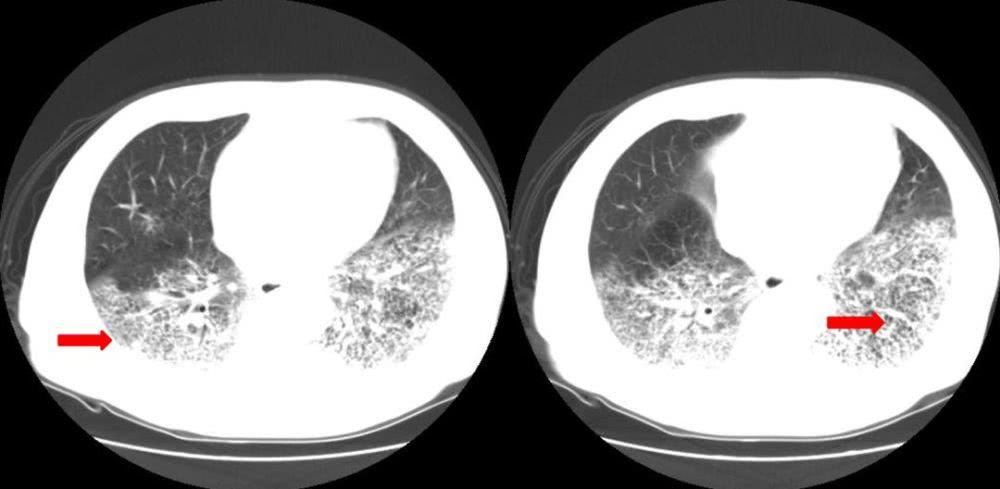

国内这边,2020 年疫情刚爆发那会,有患者在医院照 CT 的时候已经明显双肺病变,有磨玻璃状阴影。但硬是核酸检测 6 次依然是阴性。

有关专家也曾表示,CT 结果非常符合新冠肺炎但核酸检测却为阴性的病例大约占 30-40%。